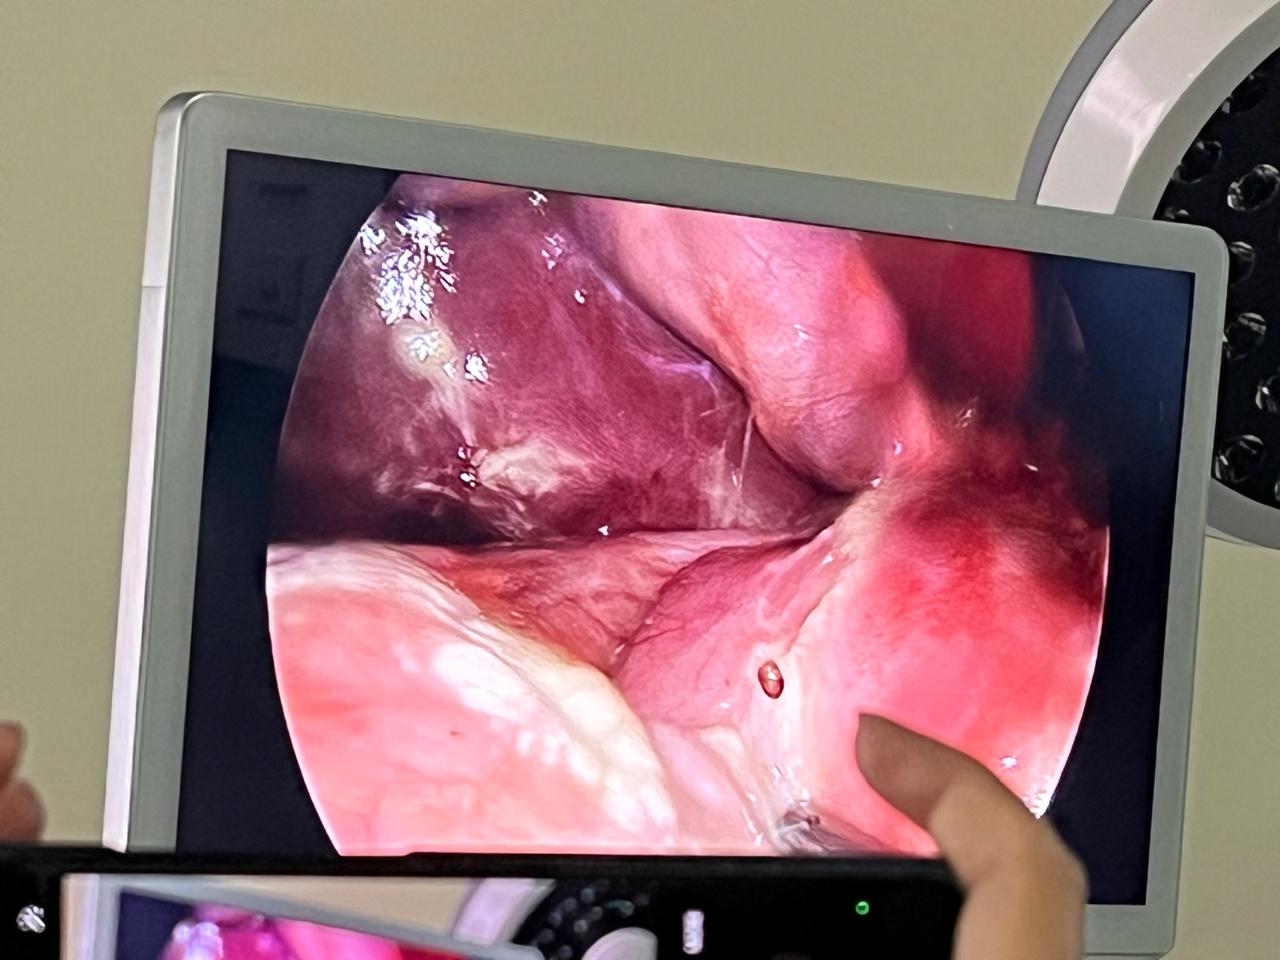

Welcome to our gallery, where you can explore a visual journey of our state-of-the-art surgical facilities, advanced medical equipment, and the exceptional care provided by our dedicated team. Here, you’ll find images showcasing our modern operating rooms, comfortable recovery areas, and the skilled professionals who ensure the highest standards of patient care.

Our gallery also features before-and-after photos of successful procedures, highlighting our commitment to transformative, evidence-based surgical practices. We invite you to browse through and witness the excellence and compassion that define our surgical practice.